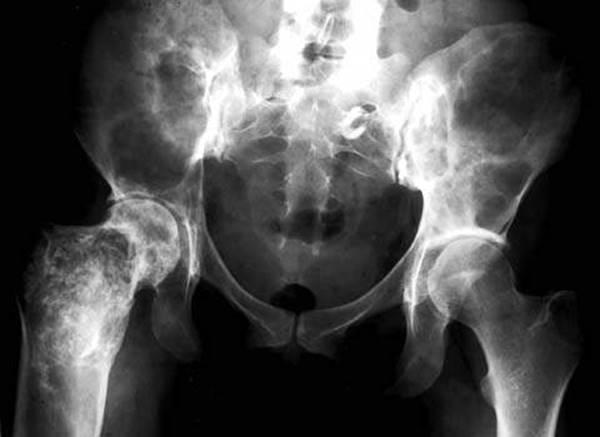

It is well established that neoplasia can arise in dysgenetic gonads. The risk of malignant tumors in dysgenetic gonads of patients with a Y chromosome depends on the nature of the disorder of sex development, the presence of the gonadoblastoma region of the Y chromosome, and other factors—both established and as yet unknown (113). A number of genes involved in gonadal differentiation were described. In the past, it was stated that the risk of malignant tumors is approximately 25%, and thus gonadectomy was recommended (114). Other perspectives suggest that a gonadal biopsy may allow the estimation of individual risk and permit a more conservative approach to gonadectomy. A multidisciplinary approach to diagnosis of disorders of sex development with attention to biological, genetic, and psychological factors is advocated (115). Functional ovarian cysts occur frequently in adolescence. They may be an incidental finding on examination or may be associated with pain caused by torsion, leakage, or rupture. Paratubal cysts represent embryologic remnants that may be confused with an ovarian mass; they are typically asymptomatic, but can be associated with adnexal torsion (Fig. 14.14). Adnexal or ovarian torsion is a challenging diagnosis to make in prepubertal girls or adolescents; torsion of a mass is more likely to occur than is torsion of normal adnexa, although this can occur. Doppler ultrasound examination may not predict the presence of torsion, although discrepancy in ovarian volume and large volume of the torsed adnexa may be helpful in making the diagnosis (116,117). Management should consist of detorsion rather than oophorectomy, even if the mass appears to have no blood flow, as recovery of ovarian function is likely (118).